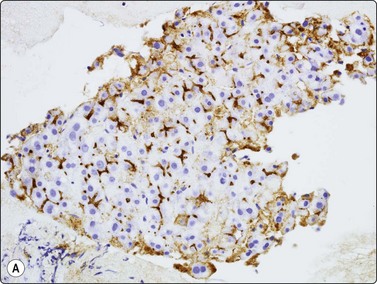

CD34 immunostaining demonstrates the classic endothelial staining pattern which is absent in reactive liver cell block (CD34, HP).

image image

Fig. 10.26 Hepatocellular carcinoma

(A) pCEA immunostaining shows cytoplasmic staining along canalicular luminal edges only (pCEA, HP); (B) HepPar-1 produces diffuse granular cytoplasmic staining in distinction to adenocarcinoma, which is negative (HepPar-1, HP).

CD34 and factor VIII immunostaining have been used in demonstrating the classic endothelial staining pattern of HCC (Fig. 10.25), absent in reactive liver and metastatic carcinoma,139 but are limited by partial staining of adenoma and focal nodular hyperplasia. Indeed, they provide little more information than the less expensive reticulin.131,139-141 Over-expression of Glypican-3, a heparan sulphate proteoglycan that plays an important role in cell growth and differentiation, has been observed in malignant hepatocytes. In several studies on cytological smears, positive staining for Glypican-3 showed a high sensitivity (80–90%) and specificity (> 95%) in HCC versus metastatic tumors and benign liver lesions.142-144

The demonstration of a characteristic bile canalicular staining pattern in HCC by means of polyclonal carcinoembryonic antigen (pCEA) is useful although it decreases with increasing anaplasia. Whereas metastatic adenocarcinoma displays full cytoplasmic immunostaining, HCC will show staining only along canalicular luminal membrane (Fig. 10.26A).73,116,129,154-158 Reported sensitivity ranges from 47% to 90%. It is essential that the polyclonal antibody be used; the same results will not be observed with the monoclonal antibody. Staining for CD10 gives the same pattern as CEA but is negative in adenocarcinoma.159,160

HepPar-1 is an antibody which recognises mitochondria in both benign and malignant hepatocytes. It has recently proved highly sensitive and specific in the distinction between adenocarcinoma and HCC, producing diffuse granular cytoplasmic staining in the latter (Fig. 10.26B).156,161,162